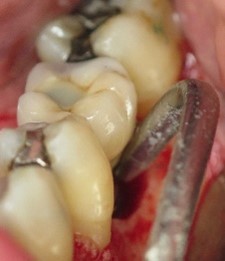

• un traitement comprenant un débridement mécanique, suivi d’un aéropolissage poudre d’air avec de la glycine (fig. 7), suivi d’un conditionnement d’acide citrique ou d’eau oxygénée à 10 volumes avec un rinçage vigoureux de la surface implantaire à l’eau stérile après chaque étape, serait capable de décontaminer la surface infectée. (Rosen et al 2018)

Figure 7: aéro polissage de la surface implantaire à l’aide d’une tête fine (Prophyflex Kavo), après élimination du tissu de granulation